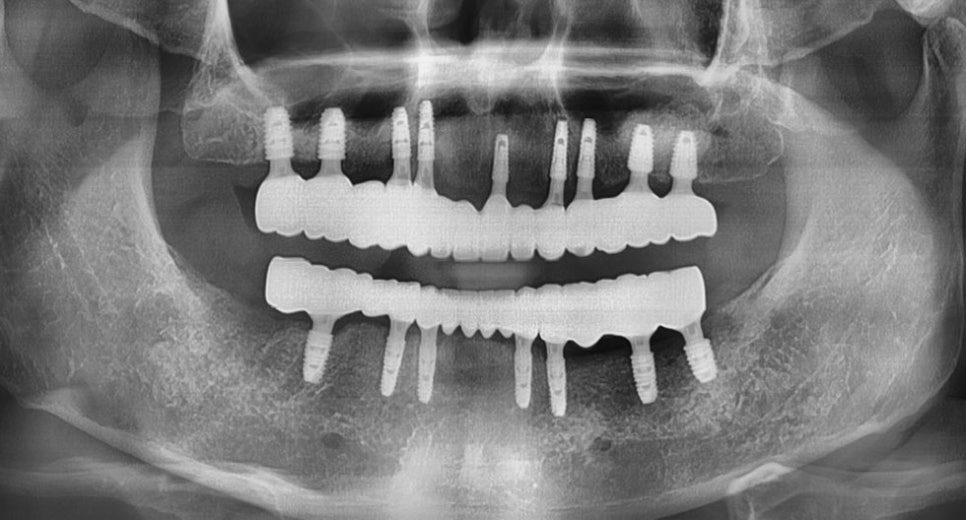

논현동임플란트잘하는곳 저희 뉴엔은

임플란트 수술 시 3D 구강스캔 및

CT, 컴퓨터 모의 수술 과정과 수술

가이드를 이용하여 출혈이 적고

명확하고 빠른 치료가 가능하도록

시행하고 있습니다.

논현동임플란트잘하는곳 저희 뉴엔의

전체임플란트 장점은 임플란트가

움직이지 않도록 임플란트와

치조골 사이를 단단히 고정하고,

식립한 임플란트와 보철물의

어긋남이 없게끔 명확도를 지향하는

튼튼한 연결을 진행합니다.